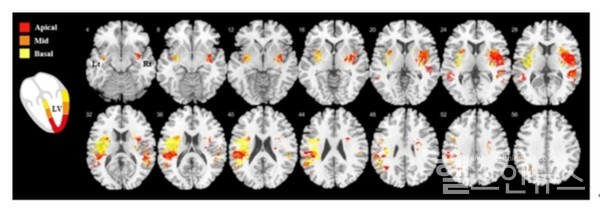

그 결과, 급성 허혈성 뇌졸중 환자 뇌의 우측 뇌섬엽(insula) 및 주변 영역과 좌측 정수리 피질(parietal cortex)이 손상된 좌심실 전반적인 종축 움직임 변화(left ventricular global longitudinal strain)와 관련이 있는 것으로 확인되었다.

뿐만 아니라 손상된 좌심실 국소 종축 움직임 변화(left ventricular regional longitudinal strain)의 분포 패턴은 관상동맥영역과는 별개로, 좌심실의 정점(apex)에서 기저부(base)로 갈수록 관련된 뇌 병변의 위치는 우반구(right hemisphere)의 경우 우측 뇌섬엽의 부리쪽(rostral)에서 꼬리쪽(caudal)으로, 좌반구(left hemisphere)의 경우 두정(parietal)영역에서 측두(temporal)영역으로 이동하는 지형학적 연관성을 확인하였다

연구팀은 또 좌심실 전반적인 종축 움직임 변화(global longitudinal strain)와 국소 종축 움직임 변화(regional longitudinal strain)와 관련된 뇌 영역을 분석함으로써, 특정 뇌 피질 부위에 좌심실 수축성과 관련된 지형학적 표현(topographical representation)의 존재에 대한 시각적 증거를 제시하였다.